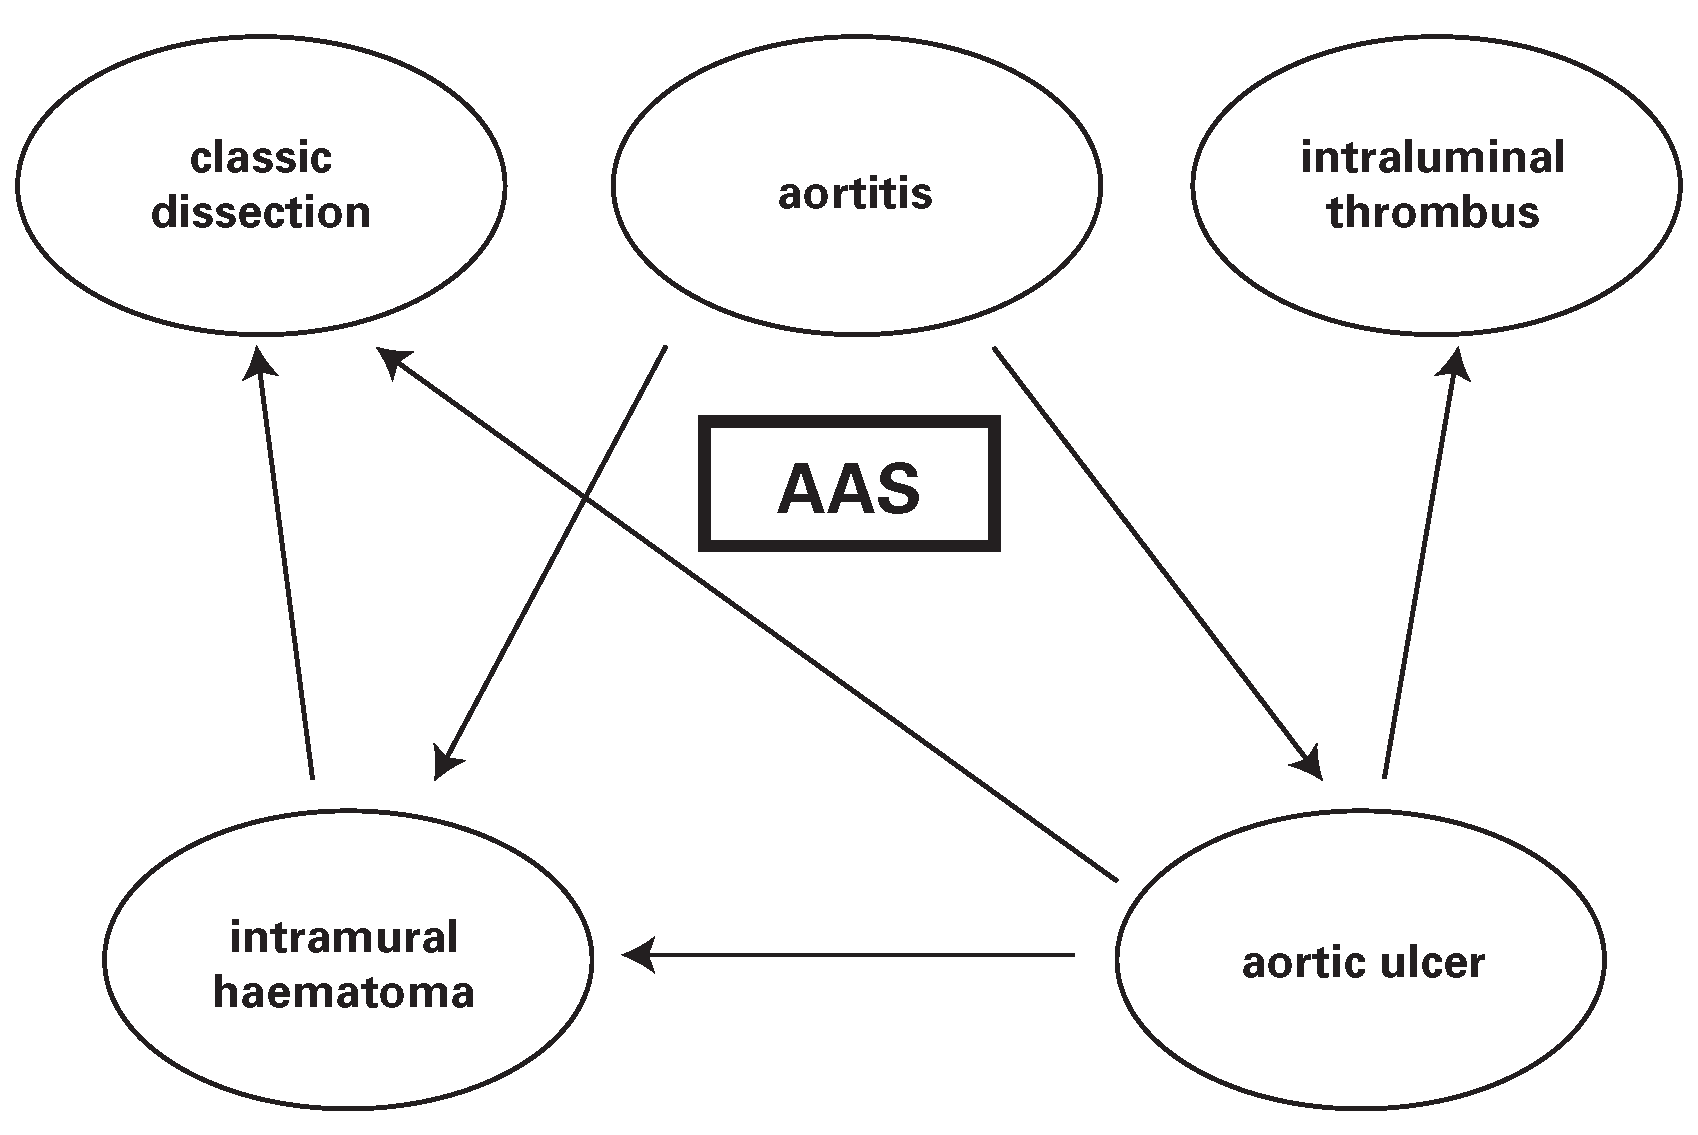

- Vilacosta, I.; San Roman, J.A. Acute aortic syndrome. Heart 2001, 85, 365–368. [Google Scholar] [CrossRef] [PubMed]

- Van der Loo, B.; Jenni, R. Acute aortic syndrome: proposal for a novel classification. Heart 2003, 89, 928. [Google Scholar] [CrossRef] [PubMed][Green Version]